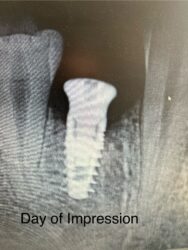

I have a patient I recently saw for an impression for an implant crown. I completed a two stage implant surgery. I didn’t note any complications at time of implant placement or uncovering.

The patient returned after three weeks for her impression. I noticed some inflammation surrounding the buccal of the healing abutment. There…

Was the healing abutment down all the way? Typically nothing should get between the healing abutment and implant if that connection is snug. I’ve seen ones where stuff gets in there with it not being down all the way.

Oral hygiene? This absolutely makes a difference when you have a fresh surgical site (even just for an uncovery) and can cause…

Hey Justin,

Thank you for sharing this case with us.

Let’s rule out some possibilities.

1. Was the healing abutment brand new? If it was brand new, was it sterile? Some docs sterilize old used healing abutments and re-use them on other patients. Unfortunately, that sometimes results in transfering debris from one patient to another, which is…